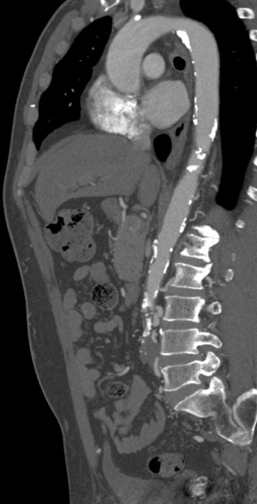

Relevant Test Results Prior to Catheterization

ABI measured on December 13, 2021, was 0.64on the right and 0.59 on the left. Duplex ultrasonography performed on August6, 2024, revealed monophasic flow in bilateral CFA, SFA, popliteal, ATA, andPTA arteries, favoring bilateral severe iliac artery disease. Subsequent CTangiography on November 15, 2024, demonstrated aortoiliac occlusive disease,without evidence of aneurysm or distal vessel obstruction. Laboratory databefore admission showed HbA1c 6.9% and LDL 76 mg/dL.

Diagnosticangiography revealed total occlusion of both common iliac arteries, while theexternal iliac arteries remained patent bilaterally. The lesions wereconsistent with aortoiliac occlusive disease (Leriche syndrome), and the distalflow was preserved via collateral circulation.

A 6F Mach1 MP guiding catheter waspositioned via aterial access. Wiring was performed sequentially with Gladius0.014¡È and Halberd 0.014¡È under NaviCross 0.018¡È catheter support, then switched to an Astato XS 40 for bettercontrol. Using a CSI microcatheter, the 0.018¡È system was exchanged for a 0.014¡È wire to performIVUS. IVUS initially could not advance but succeeded after predilatation withan Ultraverse 2.0 balloon. IVUS revealed that the lesion was locatedclose to the inferior mesenteric artery and provided accurate vessel sizing forappropriate stent selection. The system was then switched back to the 0.018¡È platform forintervention. Balloon dilatations were performed using Ultraverse 5.0 ¡¿ 80 mmfor the right and 7.0 ¡¿ 40 mm for the left common iliac artery, followed bysimultaneous kissing balloon inflation. Further expansion was achieved with Armada8.0 ¡¿ 80 mm balloons. Two VBX 8.0 ¡¿ 59 mm heparin-bonded stent grafts weredeployed in the right and left common iliac arteries. A subintimal flap belowthe right CIA stent edge required an additional VBX 8.0 ¡¿ 39 mm stent.Post-dilatation was performed with a Finestream S Plus 8.0 ¡¿ 40 mm andUltraverse 7.0 ¡¿ 80 mm balloon using the final kissing technique. Final angiography demonstrated well-expandedstents and excellent bilateral flow without residual stenosis or dissection.Both femoral access sites were closed with ProGlide devices, and the leftradial sheath was removed with manual compression.

Case Summary